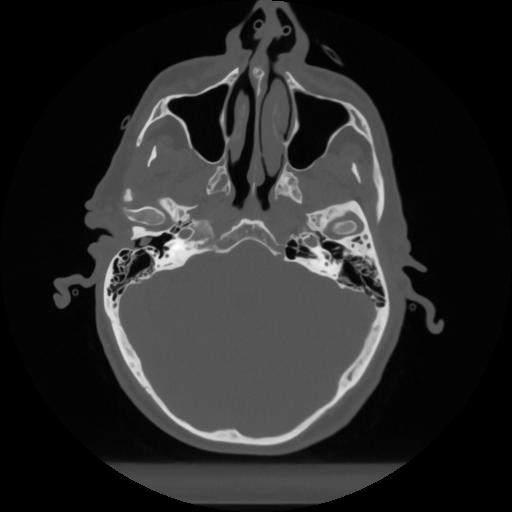

12 P.BLANDAS,,Vol,0.5,P.BLANDAS,,